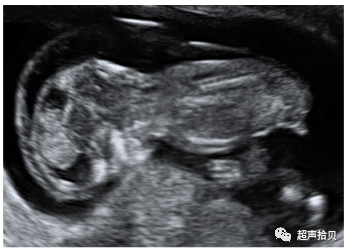

5)胎儿NT 3.5-4.4 mm

5-1)这张图片解释了如何计算NT增加的后果。我们以NT为3.5-4.4毫米的胎儿为例。

• 在12周时诊断为NT为3.5-4.4 mm的100例胎儿中,20例出现染色体异常,80例为整倍体。

• 80个整倍体胎儿中,有2个(2.5%)会在接下来的几周内死亡。

• 80个整倍体胎儿中,另有8个(10%)会出现严重缺陷。

• 其余的70个没有重大缺陷的整倍体胎儿将是活产和健康的。